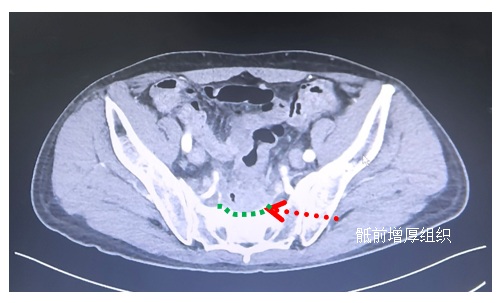

直腸癌術(shù)后骶前“假性復(fù)發(fā)”

一、定義直腸癌術(shù)后骶前復(fù)發(fā)是指直腸癌根治性切除術(shù)后,腫瘤在骶前區(qū)域(包括軟組織或骨性結(jié)構(gòu))再次出現(xiàn)的局部復(fù)發(fā)類型。骶前復(fù)發(fā)因位置深在且常侵犯周圍結(jié)構(gòu)(骶前筋膜、血管、神經(jīng)、骶骨),治療難度顯著高于其他局部復(fù)發(fā)類型。然而,臨床上時(shí)常碰到一些直腸癌術(shù)后骶前“假性復(fù)發(fā)”的病例,其臨床表現(xiàn)、影像特征均與骶前復(fù)發(fā)類似,其實(shí)際的病理機(jī)制卻是炎癥導(dǎo)致的瘢痕增生等非腫瘤性病變。二、病因與發(fā)病機(jī)制骶前假性復(fù)發(fā)的發(fā)生主要與手術(shù)創(chuàng)傷、術(shù)后修復(fù)及輔助治療相關(guān),具體機(jī)制包括:·手術(shù)創(chuàng)傷修復(fù):直腸癌手術(shù)(尤其是低位直腸癌保肛手術(shù)或腹會(huì)陰聯(lián)合切除術(shù))可能對(duì)骶前間隙造成損傷,局部出血、滲出后形成血腫或積液,后續(xù)肉芽組織增生、纖維化,在影像學(xué)上表現(xiàn)為軟組織腫塊,易被誤認(rèn)為腫瘤復(fù)發(fā)。·放療后組織反應(yīng):接受術(shù)后輔助放療的患者,骶前區(qū)域組織受放射線損傷后出現(xiàn)局部炎癥反應(yīng)、脂肪壞死、纖維結(jié)締組織增生,甚至形成放射性纖維化,表現(xiàn)為骶前區(qū)密度增高影或腫塊樣改變?!ぎ愇锓磻?yīng):手術(shù)中使用的止血材料(如止血紗布、明膠海綿)或縫線等異物,可能引發(fā)局部異物反應(yīng),形成慢性炎癥結(jié)節(jié)。·慢性炎癥刺激:術(shù)后骶前間隙感染、竇道形成或腸瘺等并發(fā)癥,長(zhǎng)期炎癥刺激導(dǎo)致局部組織增生、瘢痕形成,影像學(xué)表現(xiàn)類似腫瘤。三、臨床表現(xiàn)·癥狀缺乏特異性:多數(shù)患者無(wú)明顯自覺(jué)癥狀,部分可因局部組織增生壓迫或炎癥刺激出現(xiàn)骶尾部墜脹感、疼痛、排便習(xí)慣改變(如排便困難、便頻)、會(huì)陰部不適等,與腫瘤復(fù)發(fā)癥狀相似。·病程特點(diǎn):癥狀多呈慢性、穩(wěn)定狀態(tài),無(wú)進(jìn)行性加重趨勢(shì),且與腫瘤標(biāo)志物(如CEA、CA19-9)升高無(wú)明顯關(guān)聯(lián)(真性復(fù)發(fā)常伴隨腫瘤標(biāo)志物異常升高)。四、影像學(xué)特征骶前假性復(fù)發(fā)的影像學(xué)表現(xiàn)與真性復(fù)發(fā)有一定重疊,需結(jié)合臨床病史綜合判斷:·CT表現(xiàn):骶前區(qū)域可見(jiàn)邊界模糊的軟組織密度影,密度多較均勻,增強(qiáng)掃描后輕度強(qiáng)化或無(wú)明顯強(qiáng)化,部分可見(jiàn)條索狀纖維化改變,與周圍組織分界不清?!RI表現(xiàn):T1加權(quán)像多呈等或低信號(hào),T2加權(quán)像信號(hào)復(fù)雜(可因纖維化、炎癥或少量積液表現(xiàn)為等信號(hào)、稍高信號(hào)),增強(qiáng)掃描強(qiáng)化程度較弱且不均勻,無(wú)典型腫瘤“強(qiáng)化明顯、邊界不清、侵犯周圍組織”的特征。·動(dòng)態(tài)變化:隨訪觀察中,假性復(fù)發(fā)病灶通常無(wú)明顯增大,甚至隨時(shí)間推移逐漸縮小或穩(wěn)定;而真性復(fù)發(fā)病灶多呈進(jìn)行性增大。五、鑒別診斷六、治療與管理骶前假性復(fù)發(fā)并非腫瘤復(fù)發(fā),無(wú)需抗腫瘤治療,臨床處理以保守觀察和對(duì)癥支持為主:·保守觀察:明確診斷后定期隨訪,每3-6個(gè)月復(fù)查盆腔MRI/CT及腫瘤標(biāo)志物,監(jiān)測(cè)病灶大小及形態(tài)變化。若病灶穩(wěn)定或縮小,進(jìn)一步支持假性復(fù)發(fā)診斷?!?duì)癥治療:針對(duì)局部疼痛、墜脹等癥狀,可給予非甾體抗炎藥(如塞來(lái)昔布)或鎮(zhèn)痛藥緩解;若合并輕度炎癥,可短期使用抗生素或抗炎藥物?!け苊膺^(guò)度治療:確診后無(wú)需再次手術(shù)、放療或化療,防止因誤判導(dǎo)致的醫(yī)源性損傷(如手術(shù)創(chuàng)傷、放療并發(fā)癥)。七、臨床意義與注意事項(xiàng)·避免誤診誤治:骶前假性復(fù)發(fā)的誤診可能導(dǎo)致不必要的激進(jìn)治療(如二次手術(shù)、高強(qiáng)度放化療),增加患者痛苦及醫(yī)療負(fù)擔(dān)。臨床中對(duì)術(shù)后骶前區(qū)異常病灶需堅(jiān)持“病理優(yōu)先”原則,通過(guò)穿刺活檢明確診斷?!ぶ匾暥鄬W(xué)科協(xié)作:對(duì)于影像學(xué)不典型的病例,建議通過(guò)腫瘤內(nèi)科、外科、影像科及病理科多學(xué)科會(huì)診(MDT)綜合判斷,結(jié)合手術(shù)史、放療史、癥狀及檢查結(jié)果制定診療方案。·長(zhǎng)期隨訪管理:即使確診假性復(fù)發(fā),仍需長(zhǎng)期隨訪,因部分患者可能同時(shí)存在微小腫瘤殘留,需通過(guò)動(dòng)態(tài)監(jiān)測(cè)及時(shí)發(fā)現(xiàn)真性復(fù)發(fā)跡象。八、典型病例1、簡(jiǎn)要病史患者一年前因直腸癌在當(dāng)?shù)蒯t(yī)院行腹腔鏡直腸癌根治術(shù)。術(shù)后病理為pT2N0M0,I期。術(shù)后出現(xiàn)吻合口漏,予以抗炎、引流、營(yíng)養(yǎng)支持等保守治療后好轉(zhuǎn)出院。術(shù)后半年出現(xiàn)明顯排便困難,復(fù)查腸鏡提示吻合口充血、粗糙、狹窄呈結(jié)節(jié)樣改變。盆腔MRI提示,骶骨前緣局部密度增高并與骶前區(qū)軟組織關(guān)系密切,考慮為直腸癌術(shù)后骶前復(fù)發(fā)。患者往返多地就診,均考慮直腸癌術(shù)后骶前高位復(fù)發(fā),無(wú)法手術(shù),遂至本中心就診。2、檢查結(jié)果盆腔增強(qiáng)CT:直腸癌術(shù)后,骶前軟組織增厚。PET-CT:骶前片狀輕度異常放射性增高影,不排除腫瘤局部復(fù)發(fā)。腸鏡:進(jìn)鏡9cm見(jiàn)吻合口狹窄,腸鏡難以通過(guò),吻合口側(cè)方見(jiàn)一瘺口樣改變,予以活檢。活檢病理:吻合口潰瘍,肉芽組織增生,未見(jiàn)明確癌組織。3、MDT討論患者既往有直腸癌手術(shù)史,目前主要癥狀是吻合口狹窄導(dǎo)致的排便困難。雖然影像學(xué)提示骶前復(fù)發(fā)可能,但仔細(xì)分析,患者病理為I期腸癌,術(shù)后出現(xiàn)過(guò)明確的吻合口漏,且腸鏡活檢并沒(méi)有發(fā)現(xiàn)癌細(xì)胞,綜合考慮,患者骶前增厚組織可能為炎癥導(dǎo)致的瘢痕增生,為直腸癌術(shù)后骶前“假性復(fù)發(fā)”,決定行手術(shù)治療。4、手術(shù)方案術(shù)前留置雙側(cè)輸尿管J管,術(shù)中切除原吻合口+鏟除骶前增厚組織,送術(shù)中冰凍,明確無(wú)惡性細(xì)胞后,游離結(jié)腸脾曲,行降結(jié)腸-直腸吻合口,最后行末端回腸保護(hù)性造口術(shù)。5、術(shù)中核心指標(biāo)手術(shù)時(shí)間280min,術(shù)中出血400ml,未輸血。6、手術(shù)標(biāo)本7、術(shù)后病理原吻合口、近切緣、遠(yuǎn)切緣均未見(jiàn)癌細(xì)胞,骶前組織可見(jiàn)局部疤痕樣梭形細(xì)胞瘤樣增生。8、術(shù)后康復(fù)與隨訪患者術(shù)后恢復(fù)良好,6個(gè)月后行末端回腸造口還納術(shù),并拔除雙J管。術(shù)后隨訪1年無(wú)復(fù)發(fā)轉(zhuǎn)移,進(jìn)食排便正常。9、小結(jié)對(duì)于直腸癌術(shù)后骶前組織增厚的患者,需要注意鑒別真性復(fù)發(fā)和假性復(fù)發(fā)。其關(guān)鍵鑒別要點(diǎn)如下:o病理活檢?是金標(biāo)準(zhǔn),假性復(fù)發(fā)無(wú)惡性細(xì)胞證據(jù)。o?癥狀進(jìn)展?:真性復(fù)發(fā)癥狀呈進(jìn)行性加重,假性復(fù)發(fā)多穩(wěn)定或緩解。o腫瘤標(biāo)志物?:CEA等腫瘤標(biāo)志物水平持續(xù)升高提示真性復(fù)發(fā)。注?:若疑似復(fù)發(fā),建議盡早就醫(yī),通過(guò)多學(xué)科團(tuán)隊(duì)(MDT)制定個(gè)體化診療方案。10、后記正如虞先濬教授所說(shuō),醫(yī)德的最高境界是勇于為患者承擔(dān)責(zé)任。醫(yī)生的工作不僅是用眼睛去觀察病情,更是用心去傾聽(tīng)和理解每一位患者的需求,并努力用專業(yè)技術(shù)為患者解決疾苦。與作者取得聯(lián)系:上海長(zhǎng)征醫(yī)院周海洋周一下午特需門診周三上午專家門診